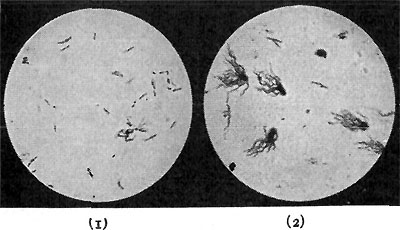

152 Disease Germs

Milk handled like this costs from two to four cents a quart more to produce than when drawn from a cow smeared with manure, in a dark, dirty, strong-smelling barn, by a milker with greasy clothing and dirty hands; and then ladled out into pitchers in the open street, giving all the dust and flies that happen to be in the neighborhood a chance to get into it! But it is doubly worth the extra price, because, besides escaping stomach and bowel troubles, you get more cream and higher food value. There is one-third more food value in clean milk than in dirty milk, because its casein and sugar have not been spoiled and eaten by swarms of bacteria. How great a difference careful cleanliness of this sort can make in milk is shown by the difference in the number of bacteria that the two kinds of milk contain. Ordinary milk bought from the wagons in the open street, or from the cans in the stores, will contain anywhere from a million to a million and a half bacteria to the cubic centimeter (about fifteen drops); and samples have actually been taken and counted, which showed five and six millions.

Such a splendid food for germs is milk, and so rapidly do they grow in it, that dirty milk will actually contain more of them to the cubic inch than sewage, as it flows in the{37} sewers. Now see what a difference a little cleanliness will make! Good, clean, carefully handled milk, instead of having a million, or a million and a half, bacteria, will have less than ten thousand; and very clean milk may contain as low as three or four hundred, and these of harmless sorts. The whole gospel of the care of milk can be summed up in two sentences: (1) Keep dirt and germs out of the milk. (2) Keep the milk cool.

BACTERIA IN CLEAN AND IN DIRTY MILK

BACTERIA IN CLEAN AND IN DIRTY MILK